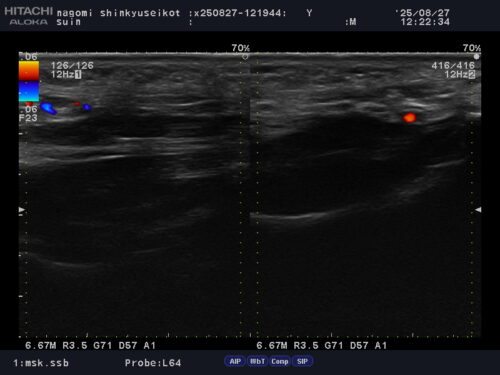

足底筋膜炎の診断にはレントゲンでは映りません。超音波エコーで患部の炎症を確認できます。

痛みを感じることが多いです。朝起こる痛みの場合でも、けい骨とひ骨を結ぶ靱帯(下記の画像)

が癒着していることが原因であることもありますので、注意が必要です。